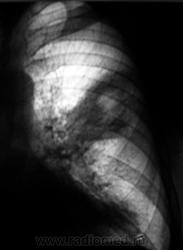

Динамика через 1,5 года.

На перый снимках двусторонняя инфильтрация (пневмония?), на последних похоже на формирующийся абсцесс в левом легком.

На первых снимках, ретроспективно, смутило повышение прозрачности левого легочного поля.

Как бы не рачок с распадом.

#18, рис. 2. - четкие признаки нарушения бронхиальной проходимости (смещение тени средостения в сторону поражения, левый купол диафрагмы выше правого, повышение воздушности правого легкого). Пока мнение мое остается прежним, однако не нравится окружающий фон (очаговость?). Дело за другими методами исследования. Можно поискать и палочки Коха, но локализация не очень подходит. Хотя, на сайте простых клинических наблюдений не бывает Жду.